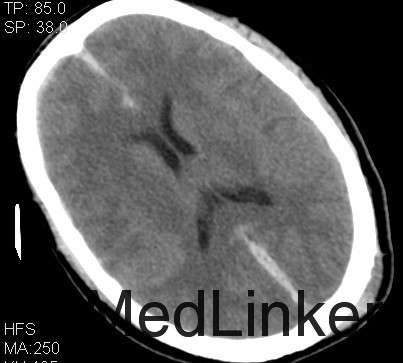

诊断:1、双侧额挫裂伤; 2、大脑镰、右侧额颞硬膜下出血;3、右额颞脑出血; 4、左枕骨骨折; 5、中枢神经系统感染 主要经过:入院后完善术前相关检查,行右侧额颞脑挫裂伤清除+去骨瓣减压+颅内压探头置入术;后行左侧额叶血肿清除+额颞顶去骨瓣减压术,术后予以抗感染、营养神经、改善循环、化痰、护胃、抗癫痫及营养支持治疗。 术后复查CT:双侧额颞顶骨局部缺如;左侧枕骨不连。 双侧额颞顶部皮下软组织稍肿胀。双侧额叶软化灶;右侧额颞部硬膜下及大脑纵裂池积液;右侧额颞部少量积气

随访+诊断:脑挫裂伤是指暴力作用于头部,造成脑组织的器质性损伤。包括挫伤和裂伤两种病理类型。它是颅脑损伤后在大体解剖和CT上最常见的一种损伤,通常为多发并伴有其他类型的颅脑损伤。脑挫裂伤可发生于受暴力直接作用的相应部位或附近,产生冲击伤,但是通常发生严重和常见的是脑挫裂伤出现在远离打击点的部位,暴力作用点的对应点,产生严重的对冲伤。由于颅骨骨折,开放性损伤容易发生颅内感染,应尽早手术治疗。